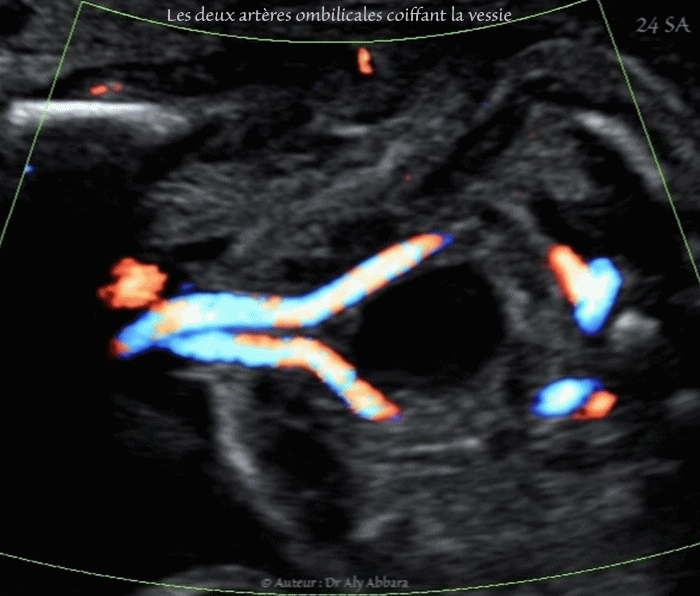

- Image échographique animée montrant, grâce au Doppler couleur de type Dynamic-Flow, les deux artères ombilicales dans leurs portions pelviennes, coiffant la vessie après leur naissance des artères iliaques internes, puis se rejoignant en avant de la vessie pour atteindre l'ombilic, puis le cordon ombilical.